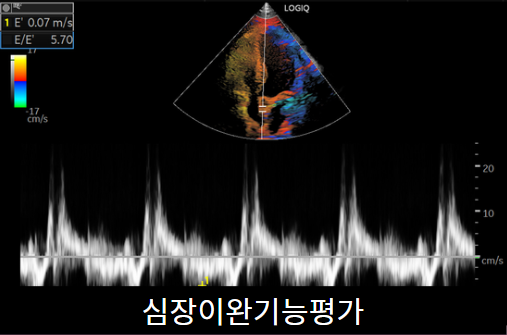

심장초음파

심장초음파는 흉통, 호흡곤란이 있을 때 심장의 구조적 이상을 평가하기 위해 시행합니다. 심근경색, 판막질환, 심부전을 진단하는데 많은 정보를 제공하는 검사입니다. 약 20~30분 걸립니다.